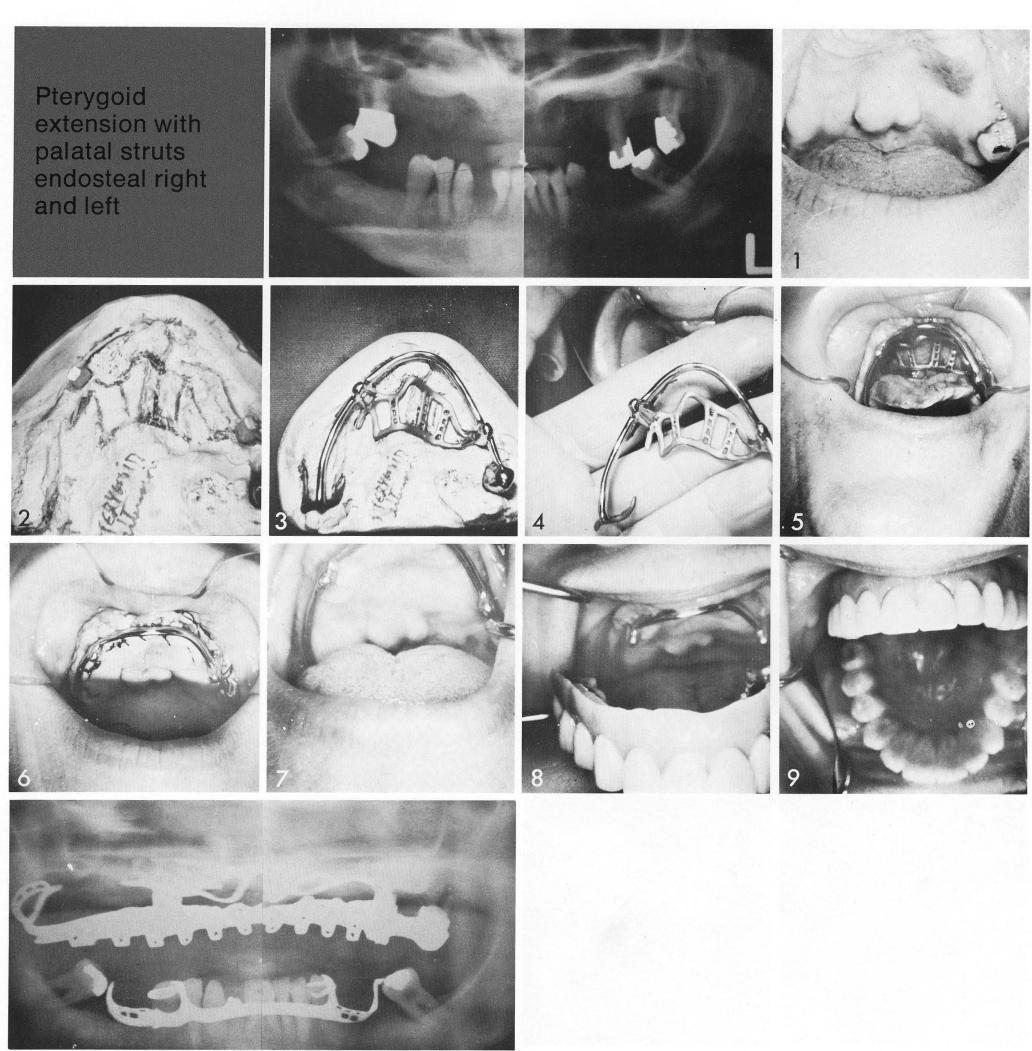

Pterygoid extension with

palatal struts endosteal righ and left

In this somewhat unusual old pterygoid extension case, one posterior abutment is a natural tooth—the only tooth remaining in the arch (I). The large torus and uneven ridge resorption were also noteworthy in this case, forcing unusual, unbalanced placement of the blodevents (2). The pterygoid extension implant, and older design (3,4), covered a good portion of the palate, requiring extensive exposure (5) of the palatal surface for seating the implant. The tissues were closed under the bar (6), and allowed to heal (7). The clip-on denture (8), without a bothersome palatal portion (9), attaches to the bar.

1 Large palatine torus and uneven maxillary ridge resorption for implant